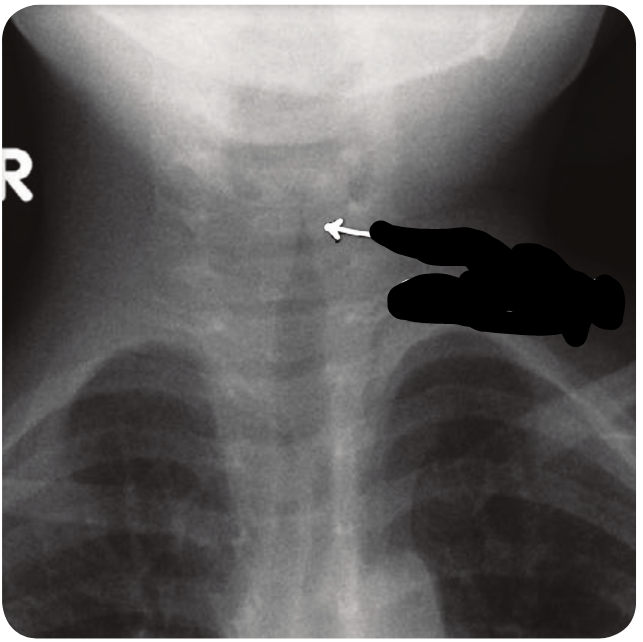

מהו הממצא

Steeple sign

היצרות של הטרכיאה , קנה צריח

מאפיין Croup